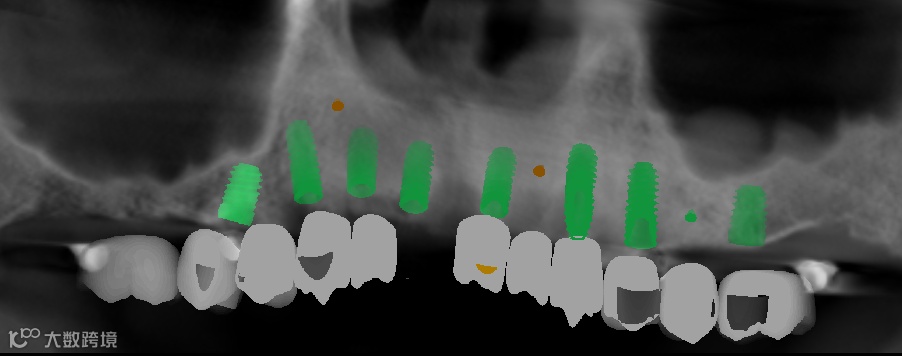

数字化种植手术规划与导板设计

临床种植手术过程